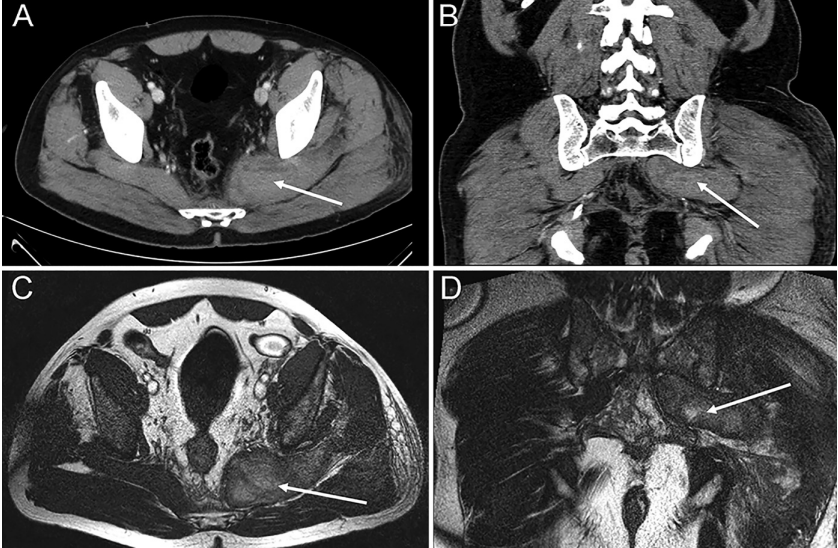

当天晚些时候,由于左侧 S1 神经根疼痛的进展,患者被送进了他所在的地区医院。他接受了第二次臀内镇痛剂注射,并被转移到当地医院的内科接受进一步治疗。第二天(住院第 2 天),患者出现左下肢肢端无力和排尿困难。住院第 3 天,患者出现尿潴留、勃起功能障碍、鞍区感觉迟钝、L5 和 S1 感觉迟钝,以及膝关节远端运动障碍。他被转回地区医院以排除 CES。住院第 4 天进行磁共振成像 (MRI),但未显示椎管内的神经受压。电生理检查显示骨盆区域有坐骨神经神经病变的迹象,随后进行了骨盆CT扫描显示梨状肌增大(图 1A 和 B )。

图1 A:轴向术前CT显示梨状肌内血肿(白色箭头)。B:冠状术前CT显示梨状肌内血肿(白色箭头)。C:轴向术前 MRI T2 序列显示梨状肌内的血肿(白色箭头)。D:冠状术前 MRI显示梨状肌内的血肿(白色箭头

在住院的第 5 天在神经外科就诊,然而由于神经外科没有关于之前臀肌注射过的止痛剂的信息,进行了盆腔区域的MRI扫描以排除肿瘤性病变。MRI 结果表明梨状肌内有血肿(图 1C 和 D)。患者凝血功能障碍得到纠正,住院第6天立即进行血肿清除术。